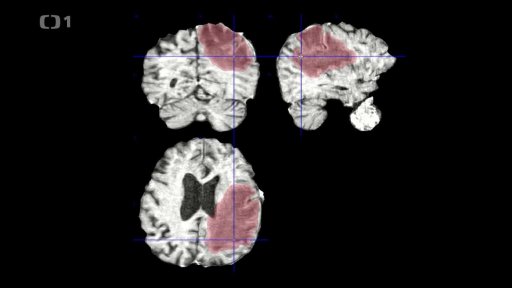

Dva roky od tornáda — O vědě a vědcích: Umělá inteligence v onkologii — Baťovský mural — Tři minuty z Drnovic — Nová kašna — iReportéři — Bez komentáře: Obce dva roky po tornádu